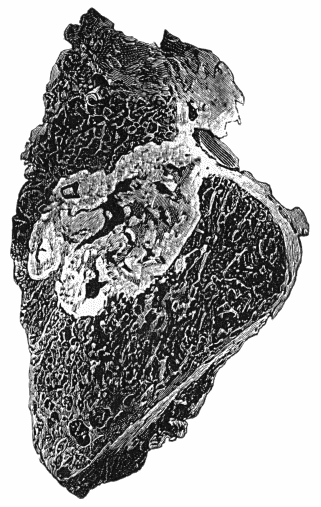

114.Section through Gouty Bursa 428

156.Caseating focus in Upper End of Fibula 513